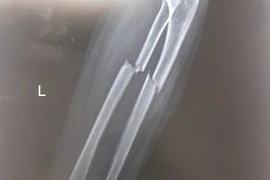

Bé trai 7 tuổi gãy xương cẳng tay, suýt mất vận động sau cú ngã xe đạp

Gãy kín hai xương cẳng tay có di lệch, nguy cơ biến dạng, hạn chế vận động. Phẫu thuật kết hợp xương giúp khôi phục vận động, tránh biến chứng cứng khớp.